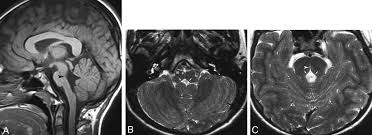

Neuroimaging (preferably magnetic resonance imaging of the brain with and without contrast) can help with both localization of the lesion and determination of etiology, especially if vascular or neoplastic in nature. If an infectious cause is suspected, consider serum and CSF testing for common chronic infections such as tuberculosis and syphilis. Whipple disease diagnosis requires special periodic acid-Schiff (PAS) stains of pathologic samples or PCR, typically obtained from the gastrointestinal tract or other affected tissues. In regard to metabolic conditions, such as Niemann-Pick type C, work-up may include serum transasminase evaluation, skin fibroblast assays for sphingomyelinase activity, and possibly genetic testing.